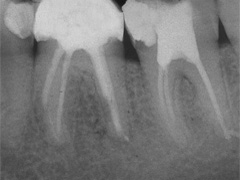

Keine 8 Wochen gingen noch in's Land, bis das mit Macht geschah, was lange schon erwartet war. Das Arbeitsprogramm bestand aus Eröffnung von Zahn 34 und einer Schwellung inkl. Drainage, am nächsten Tag dann noch Aufbereitung des Kanals mit Einlage. 2 Wochen später dann die Füllung plus einem als Resektion deklarierten Auslöffeln des Granu­lationsgewebes durch eine Mini-Öffnung, zu deren Verschluss eine Naht genügte.

3 Aufnahmen sind von 2001, die vierte vom Nov. 2006